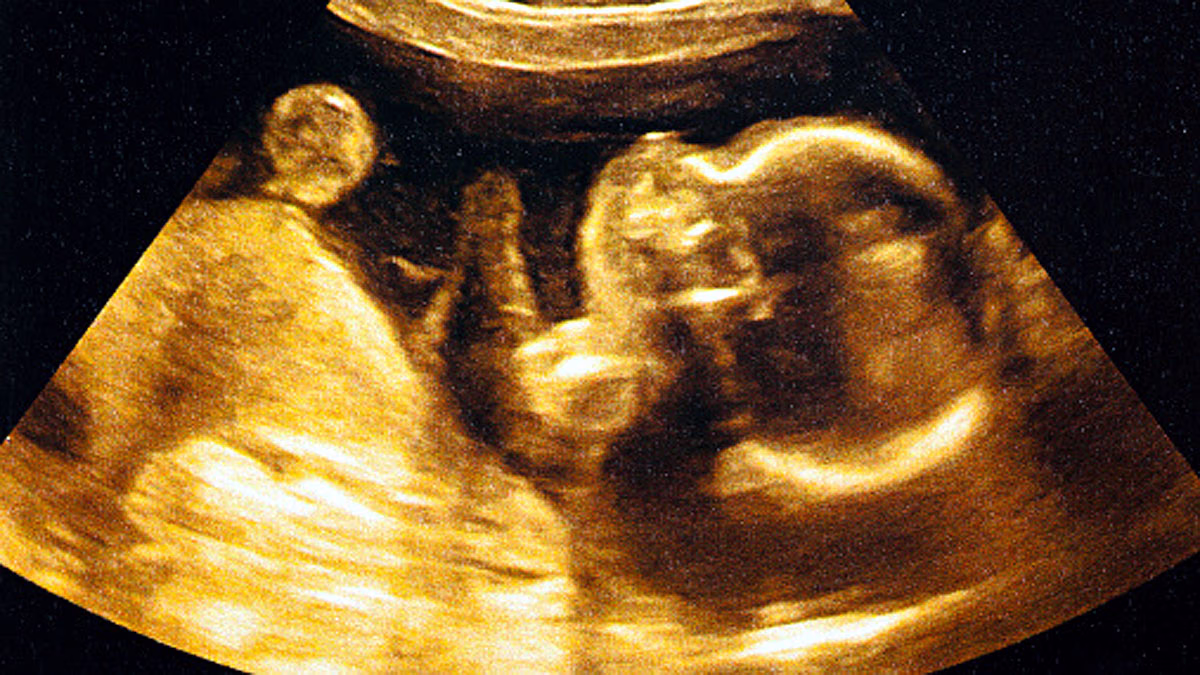

Impact of Pollution on Unborn Children

Unborn children or fetuses are the most vulnerable victims of pollution. When a mother lives in polluted environments, toxic particles (like dust and smoke) transfer from her body to that of her child, significantly reducing the child’s survival odds.

• Stillbirth: The baby dies in the womb.

• Low Birth Weight: Babies are born small and weak.

• Preterm Birth: Babies are delivered prematurely, often weak.

Scientific studies highlight how pollution affects maternal lungs, diminishing oxygen and nutrients supplied to the fetus, stunting lung development in the womb, and leading to respiratory diseases later. Fine particulates provoke inflammation in mothers, weakening their immune systems.